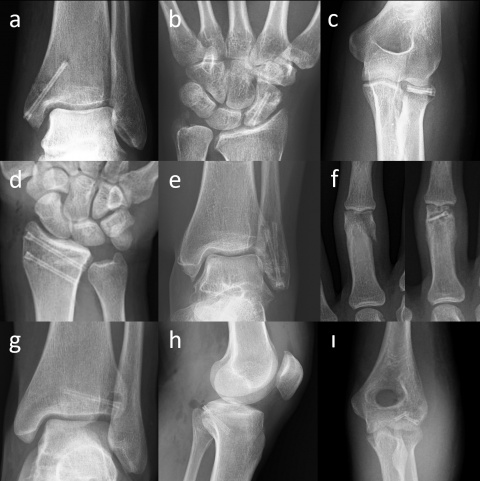

Die Mg-Kompressions-Schraube MAGNEZIX® CS kann für eine ganze Reihe unterschiedlicher Indikationen in der orthopädischen und der Trauma-Chirurgie eingesetzt werden (Abbildung 1): grundsätzlich ist sie geeignet für die Versorgung von Frakturen und Pseudoarthrosen sowie Arthrodesen kleiner Knochen, im Speziellen Kahnbeinfrakturen, Abrissfrakturen, Sprunggelenksfrakturen, intraartikuläre Frakturen der Fußwurzel- und der Mittelfußknochen, der Handwurzel- und Mittelhandknochen, Bunionektomien und Osteotomien am Fuß oder Knöchel, Arthrodesen kleiner Gelenke (z. B. Phalangen), Patella-Frakturen, distale Ulna und Radiusfrakturen, Radiuskopffrakturen und intraartikuläre Frakturen des distalen Humerus [13].

Magnesium-Kompressionsschrauben. (a) Mediale Spunggelenksfraktur

(b) Kahnbeinfraktur (c) Radiuskopffraktur (d) Distale Radiusfraktur (e)

Laterale Spunggelenksfraktur (f) Fingerfraktur (g) Tillaux-Fraktur im

Jugendalter (h) Abriss des hinteren Kreuzbands (ı) Capitulum-humeri-

Fraktur